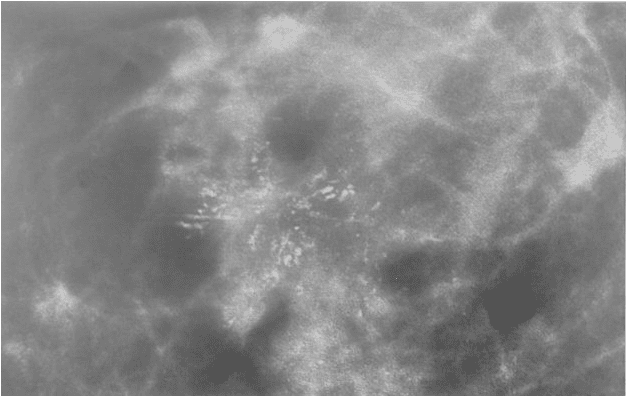

Meme kanserinin en erken bulgusu olan küçük kireçlenme odaklarını gösterebilen tek görüntüleme metodu mammografidir. Meme kanserinin büyüyüp ele gelecek şekilde kitle ya da meme cildinde değişiklik oluştutmasıyla, elle veya gözle hasta tarafından farkedilmesi, kanserin oluşmasından yıllar sonraya denk gelir. Yani, bu aşamaya gelmiş bir meme kanserinın vücuda yayılması için, yeterince uzun bir süre geçmiş demektir. Bu nedenle kanserin başlangıç aşamasında yakalanması büyük önem taşır.